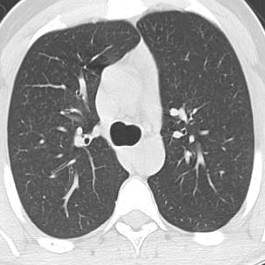

We propose a novel continual self-supervised learning (CSSL) framework for simultaneously learning diverse features from multi-window-obtained chest computed tomography (CT) images and ensuring data privacy. Achieving a robust and highly generalizable model in medical image diagnosis is challenging, mainly because of issues, such as the scarcity of large-scale, accurately annotated datasets and domain shifts inherent to dynamic healthcare environments. Specifically, in chest CT, these domain shifts often arise from differences in window settings, which are optimized for distinct clinical purposes. Previous CSSL frameworks often mitigated domain shift by reusing past data, a typically impractical approach owing to privacy constraints. Our approach addresses these challenges by effectively capturing the relationship between previously learned knowledge and new information across different training stages through continual pretraining on unlabeled images. Specifically, by incorporating a latent replay-based mechanism into CSSL, our method mitigates catastrophic forgetting due to domain shifts during continual pretraining while ensuring data privacy. Additionally, we introduce a feature distillation technique that integrates Wasserstein distance-based knowledge distillation (WKD) and batch-knowledge ensemble (BKE), enhancing the ability of the model to learn meaningful, domain-shift-robust representations. Finally, we validate our approach using chest CT images obtained across two different window settings, demonstrating superior performance compared with other approaches.